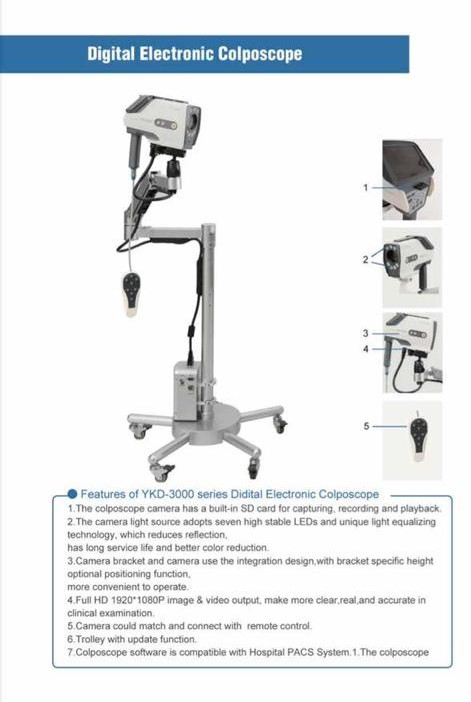

Video Colposcope With Swing Arm stand basic

Video Colposcope With Swing Arm stand basic

DIGITAL COLPOSCOPE

DIGITAL COLPOSCOPE